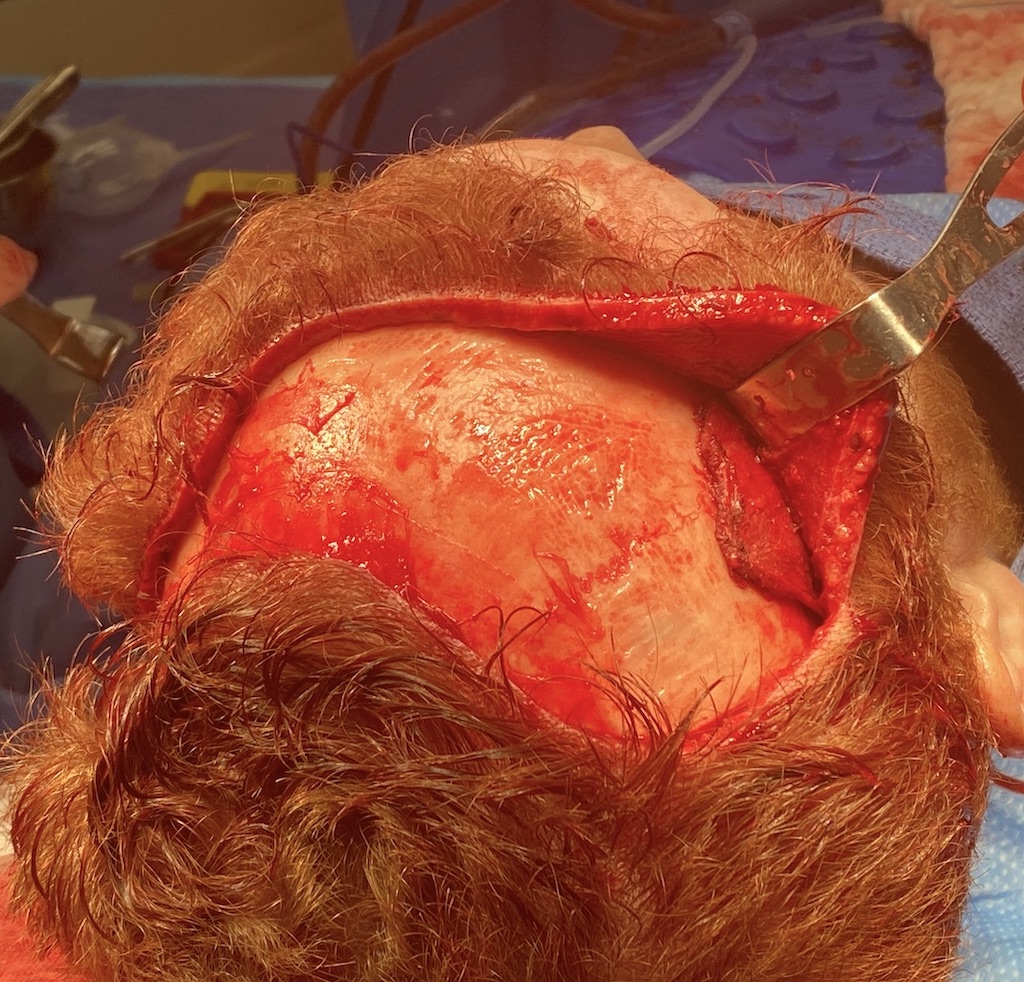

Severe narrowing skull deformity from prior sagittal craniosynostosis repair as an adult.

Complete replacement of entire skull by a custom implant with temporal fat injections.

Severe narrowing skull deformity from prior sagittal craniosynostosis repair as an adult.

Complete replacement of entire skull by a custom implant with temporal fat injections.